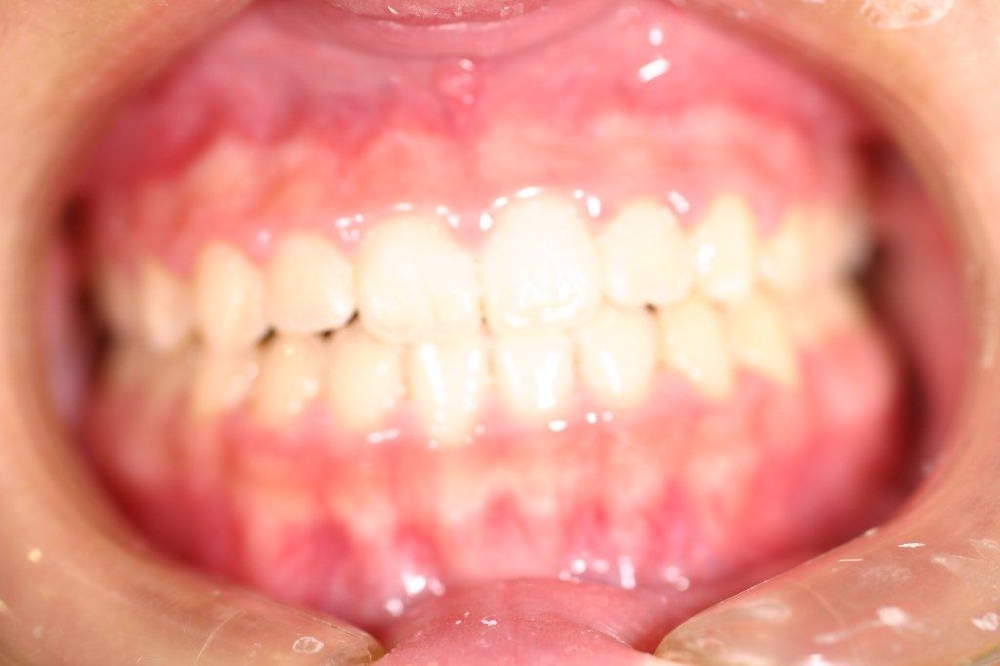

開口症例を綺麗に治した症例

Before

After

年齢 20代

治療期間 2年

治療費用 1,000,000円

治療のリスク 特になし